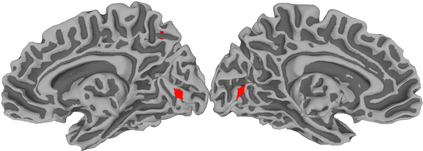

Functional Magnetic Resonance Imaging (fMRI) maps cerebral activation in response to stimuli but this activation is often difficult to detect, especially in low-signal contexts and single-subject studies. Accurate activation detection can be guided by the fact that very few voxels are, in reality, truly activated and that these voxels are spatially localized, but it is challenging to incorporate both these facts. We address these twin challenges to single-subject and low-signal fMRI by developing a computationally feasible and methodologically sound model-based approach, implemented in the R package MixfMRI, that bounds the a priori expected proportion of activated voxels while also incorporating spatial context. An added benefit of our methodology is the ability to distinguish voxels and regions having different intensities of activation. Our suggested approach is evaluated in realistic two- and three-dimensional simulation experiments as well as on multiple datasets. Finally, the value of our suggested approach in low-signal and single-subject fMRI studies is illustrated on a sports imagination experiment that is often used to detect awareness and improve treatment in patients in persistent vegetative state (PVS). Our ability to reliably distinguish activation in this experiment potentially opens the door to the adoption of fMRI as a clinical tool for the improved treatment and therapy of PVS survivors and other patients.